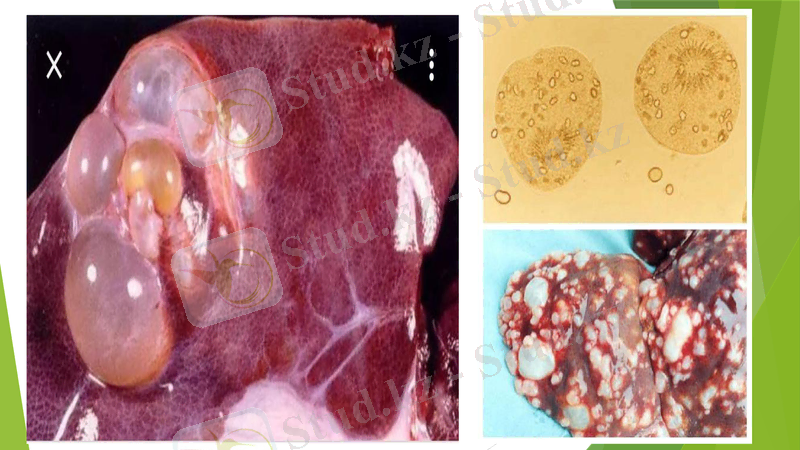

Эхинококк көпіршіктері өте баяу өседі және баланың басының мөлшеріне жетуі мүмкін.

ПАТОЛОГИЯЛЫҚ ӨЗГЕРІСТЕР. Қарқынды инвазия кезінде органдардың күрт өсуі орын алады: шошқадағы бауырдың салмағы 32 кг-ға дейін, ал ірі қара малда - 64 кг-ға дейін артады. Зақымдалған мүшелерде әртүрлі мөлшердегі көпіршіктер кездеседі, олардың беті бұдырлы, біркелкі емес. Интенсивті цестодты инвазиясы бар етқоректілердің жіңішке ішектерінде катаральды энтерит және иммагинальды эхинококктар, сонымен қатар цестодтардың басқа түрлері кездеседі.